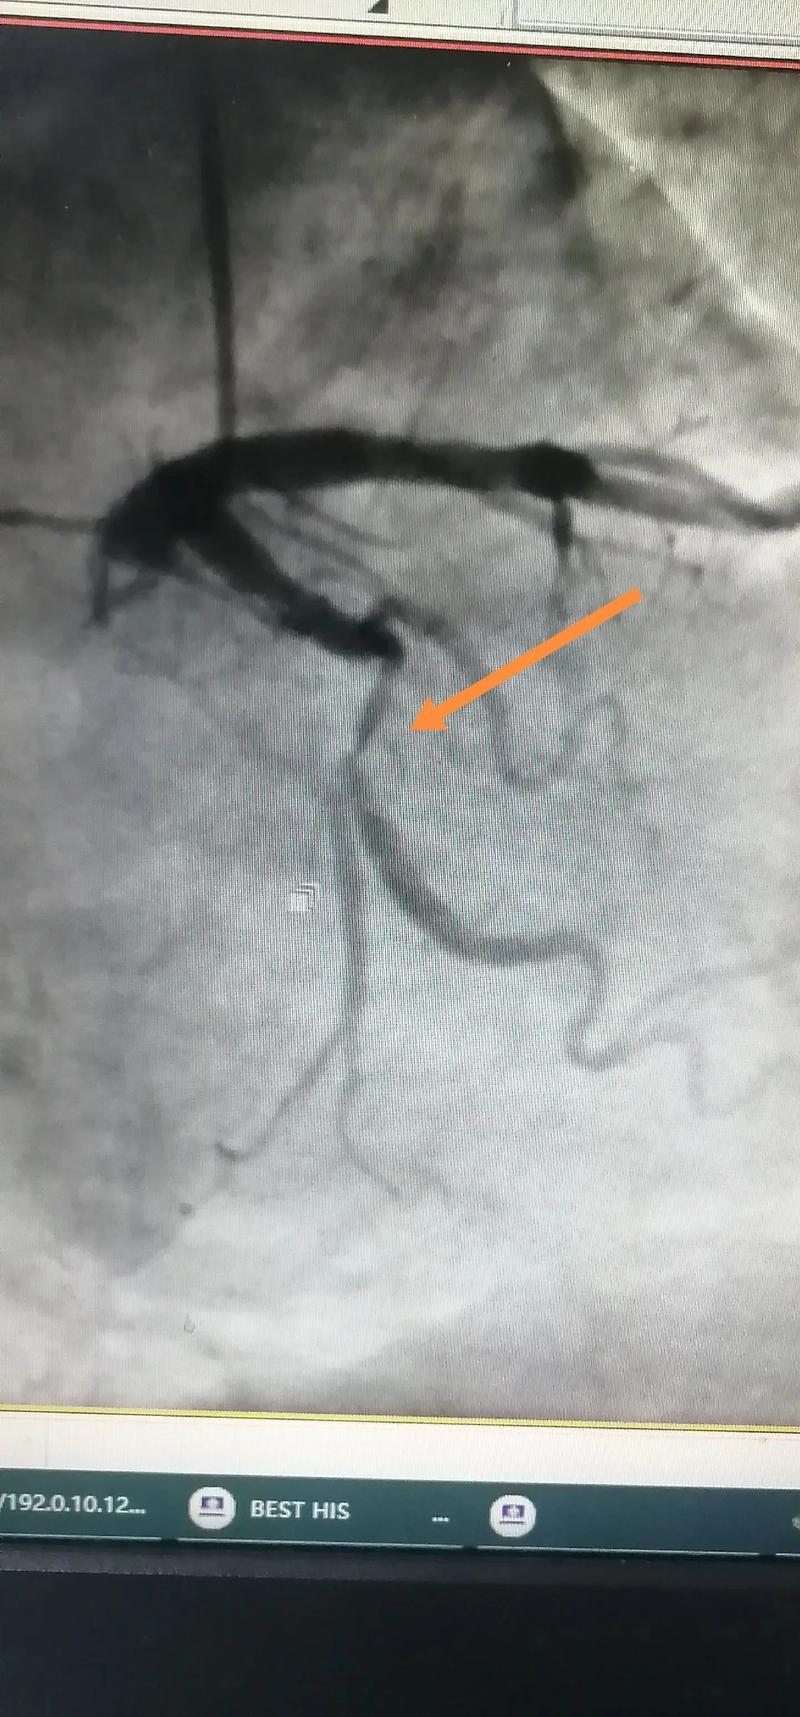

4、做了冠脉造影不会导致患者存活期变短冠脉造影是诊断冠心病的重要手段,通过向冠状动脉内注入造影剂,利用X线显影技术清晰显示血管的形态走行及病变位置其核心目的是明确冠状动脉是否存在狭窄堵塞等病理改变,为后续治疗提供关键依据该检查虽为有创操作,但风险可控可能出现的并发症包括穿刺部位出血。